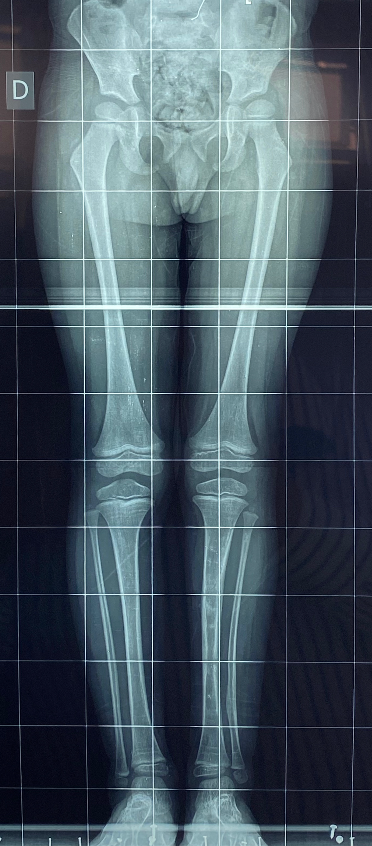

As malformações congênitas exigem abordagem individualizada, considerando idade, potencial de crescimento e função. O plano terapêutico combina fisioterapia, órteses e, quando indicado, cirurgia reconstrutiva staged. Técnicas incluem epifisiodese para controle de crescimento, alongamento ósseo gradual com fixador externo ou haste motorizada, transferências tendíneas, osteotomias direcionadas e reconstrução articular. Em deficiências longitudinais, pode-se realinhar segmentos, estabilizar o quadril/joelho/tornozelo através de técnicas de reconstrução articular como Superhip, Superknee, Superankle e otimizar o apoio plantar. O objetivo é alinhar, equalizar comprimentos e melhorar a marcha, preservando o máximo de tecido nativo e respeitando marcos de desenvolvimento.

As displasias ósseas são alterações no crescimento e na estrutura dos ossos que podem causar deformidades, encurtamento dos membros superiores e inferiores e causam limitações de função e estética. Em casos mais graves, o osso cresce torto ou enfraquecido, exigindo tratamento especializado.  O método de reconstrução óssea é a principal opção nesses casos. Ele utiliza fixadores externos, como o Ilizarov ou o TL-Hex, ou implantes internos que permitem corrigir deformidades e alongar o osso de forma gradual e segura. Após um corte controlado (corticotomia), o osso é separado milímetro a milímetro, e o corpo forma novo tecido ósseo entre as partes, recuperando o alinhamento e o comprimento natural. Um exemplo é a displasia fibrocartilaginosa focal, em que parte do osso é substituída por tecido fibrocartilaginoso, causando encurvamento progressivo e encurtamento. O tratamento com reconstrução óssea permite realinhar o membro, restaurar o comprimento e melhorar a função. O objetivo final é reestabelecer a forma, o equilíbrio, o movimento, devolvendo ao paciente melhor qualidade de vida.

A acondroplasia é a displasia mais comum e uma condição genética que causa alterações no crescimento dos ossos longos, resultando em baixa estatura e membros encurtados, mas desenvolvimento intelectual preservados. Podem ocorrer deformidades e limitação da marcha e dos membros superiores. O tratamento pode ser medicamentoso e cirúrgico, conforme a idade e a gravidade. Já existem medicamentos como o vosoritide, que atuam diretamente sobre o crescimento ósseo, estimulando o alongamento das cartilagens de crescimento e reduzindo o ritmo de deformidades em crianças. Nos casos com encurtamento mais acentuado ou deformidades já estabelecidas, o tratamento cirúrgico é o mais indicado. As opções incluem o método de reconstrução óssea com fixadores externos (como o monolateral e o hexapodal) ou o uso de hastes motorizadas de alongamento intraósseo, que permitem alongar o osso de forma controlada e discreta, sem estrutura externa visível. Ambos os métodos utilizam o princípio biológico da distração osteogênica, em que o osso é gradualmente separado após uma osteotomia, formando novo tecido ósseo. O objetivo do tratamento é melhorar a proporção corporal, corrigir deformidades, ampliar a função dos membros com maior independência e qualidade de vida.